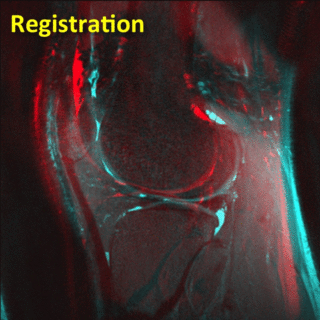

Registration

3D registration is performed to align the two sets of images. This makes comparison and analysis of longitudinal (time-series) data more robust and accurate.